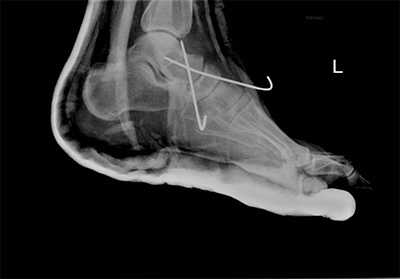

Рис. 10. Чрезкожная фиксация костей предплюсны после вправления вывиха в суставе Шопара, стопа в гипсовой лонгете

После осмотра в отделении ортопедии №2 ГКБ №13 принято решение о проведении операции - открытому устранению вывиха, артродезе 1-2-3 плюсне-клиновидных суставов, 1 межклиновидного сустава при помощи винтов и пластины, трансартикулярной фиксации спицами 4-5 плюсне-клиновидных суставов.

После восстановления 2 луча выполняем артродез межклиновидного сустава и 1 плюсне-клиновидного сустава. Учитывая что основная нагрузка ложится на 1 луч, дополнительно стабилизируем его при помощи пластины.

В стационаре пациент находится первые 2 суток после операции. Это необходимо для купирования болевого синдрома, и контроля послеоперационной раны. На 3 сутки пациент выписывается домой в гипсовой лонгетной повязке, на костылях. На ногу наступать нельзя до 6 недль после операции. Послеоперационные швы снимаются через 2 недели, лонгетная повязка при этом может быть заменена на циркулярный обычный или пластиковый гипс или ортез.